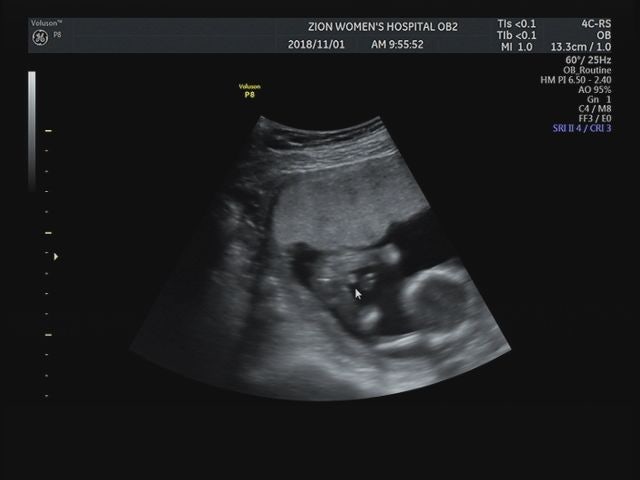

2차 기형검사 시간이라 정기검진 당일 라움산부인과에 다녀왔습니다

4주만에 만난 우리 아기♡ 해골도 귀엽고 척추도 귀엽네요. 원래 성별이 궁금했는데 호박 자세가 안좋아서 잘 안보이더라구요. . . 예전에 확인해보니 공주님이라는 암시가 있었는데 B-초음파가 수탉 같다고 하더군요. 제 80% 추측은 호박이 왕자님 닮았네요 ㅎㅎ 수탉이라는 말에 안심! 17주 산모팬티 라라트렁크, 친구방문, 하기스맘Q 임신선물 최근 배가 날로 달라지고 평소에 입던 팬티가 갑자기 불편해요. . . 인스타그램에서 어떤 분이 최근에 출시된 듯한 라라트렁크라는 팬티를 봤는데 2XL까지 나오는데 임산부용 팬티라고 광고를 해서 예비엄마가 사주셨어요. 박스색상이 달라서 직관적이네요 색상별로 고급스러운 라라트렁크 친환경박스 포장만 봐도 주인분이 배우이신걸 알수있어요 ㅎㅎ 비만임산부 추천, 날씬한 사람도 입기 최고! 강릉에서 함께 휴가를 보내고 오랜만에 만나서 너무 즐거웠어요! ! 사진은 남편이 포켓볼 기술 수업을 받고 있는 모습이다. ! Giggling Haggis Mom Qbox 배송 2장 분량을 받았는데 신청 방법을 모르겠습니다. 임신 18주, 생선과 과일 사기, 육아일기 쓰기, 성장사진첩 만들기, 임신 18주 새아기♡ 남편과 나는 매일 행복한 마음으로 호박을 기다립니다. 만났을 때 그 어느 때보다 안정감과 온전함을 준 것 같아요 ㅎㅎ 물론 그 느낌을 평생 간직하려면 서로의 많은 배려와 노력이 필요하지만 요즘은 자꾸자꾸 떠들다보니.. 어느날 문득 생선구이가 땡겨서 테이크아웃을 기다리다가 냉장고에 있던 초당두부 한그릇을 만들어 두부를 삶았습니다. 텅 빈 하루! 호박이 더 많았으면 좋겠습니다. . . ♡ 며칠 후 과일이 너무 땡겨서 오렌지, 망고, 용과, 딸기, 체리를 많이 샀어요. 하얀 딸기가 복숭아 맛이 난다고 해서 샀는데 달고 맛있어요~! 사실 수박, 복숭아 같은 여름 과일이 너무 먹고 싶은데 마트에서 살 수가 없어서 아쉬워요. 그래서 천안호두휴게소에서 점심 먹으러 ㅋㅋㅋ 따라갔죠? ? 에… !남편이 국물에 고기가 없어서 바람핀다고 하더라구요 ㅎㅎ ) 하나, 물고기가 헤엄치는 것 같아서 너무 신기했어요. 사진도 기간별로 정리해서 모아봤어요! 올 여름에 나왔던 호박 사진의 추억을 인화할 생각을 하니 또 하루가 새롭네요. 150일 만에 만난 호박… 아직 서툴지만 준비할게 자기야! 🙂